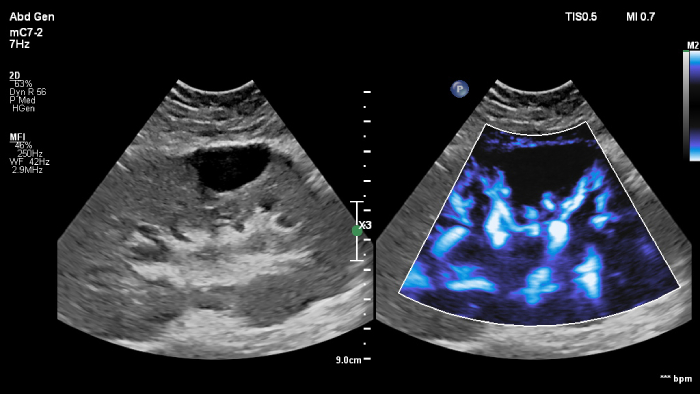

Philips ultrasound systems for interventional radiology support a range of sophisticated capabilities for interventional applications. Streamlined workflow allows clinicians to achieve fast and effective fusion of CT/MR/PET/CBCT with live ultrasound, while needle navigation aids in guiding biopsy and ablation of small and difficult-to-access lesions. Fusion and navigation can also be used in conjunction with Contrast-Enhanced Ultrasound (CEUS), giving clinicians access to even more powerful diagnostic tools with advanced visualization.